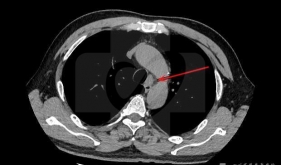

纵膈肿瘤是一组起源于纵膈的肿瘤,常见的有神经源性肿瘤、胸腺瘤、各类囊肿、淋巴瘤和生殖细胞肿瘤等,一经确诊,无论有无症状,都应考虑手...

• 纵隔镜检查

概述纵隔镜是一种特殊用途的内镜,是在喉镜及硬质支气管镜和硬质食管镜等内镜基础上发展起来的专门用于纵隔检查的内镜。由于纵隔特殊的解剖...